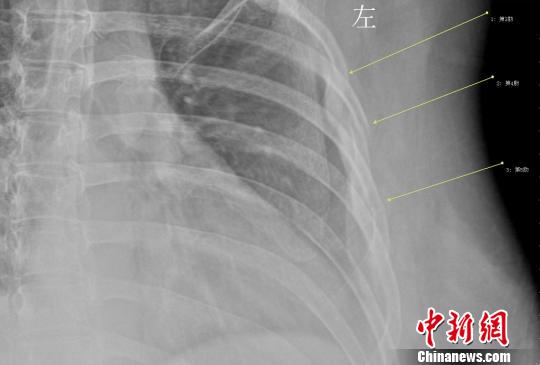

年輕女白領(lǐng)因咳嗽導致三根肋骨骨折 劉姍姍 攝

拍片結(jié)果顯示,她的第3、4、5肋骨骨折,胸外科醫(yī)生給她上了胸帶固定,并給予了止咳鎮(zhèn)痛的藥物治療。胸外科徐家行醫(yī)生詳細詢問病史,在排除了其他因素后,考慮還是咳嗽引起的肋骨骨折。